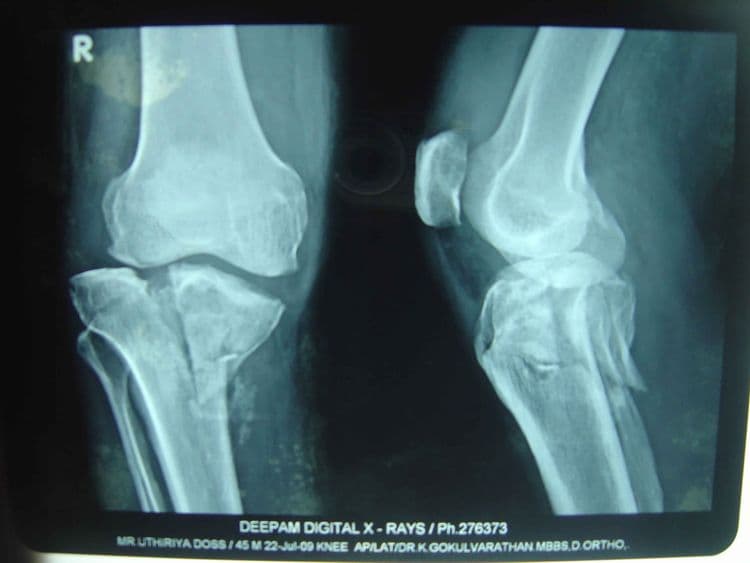

IntraArticular Fracture - हाडासोबतच सांध्याचा पृष्ठभाग सुद्धा फ्रॅक्चर होणे.